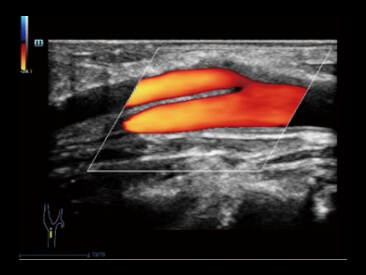

Zupe?nie nowy spos├│b na prezentacji przep?ywu krwi

z wykorzystaniem techniki Color/Power Doppler 2D w wizualizacji 3D

Przypadek kliniczny z wykorzystaniem technologii Glazing Flow (tryb power):

Unaczynienie nerki

Technologia Glazing Flow zapewnia wyra?n? wizualizacj? struktury t?tnicy ?ukowatej i t?tnicy mi?dzyp?atowej mniejszej z widokiem 3D.